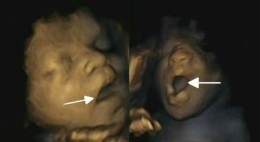

O feto a abrir a boca (à esquerda) e a bocejar, numa imagem captada pela equipa britânica

Os vídeos provam-no: o bebé, ainda na barriga da mãe, já boceja. À medida que o feto se vai desenvolvendo e a gestação se aproxima do fim, os bocejos decrescem e não há grandes diferenças entre rapazes e raparigas na frequência com que o fazem.

Em traços gerais, estas são as principais conclusões do estudo de uma equipa britânica, publicado na revista PLoS ONE, que assim pretende pôr um ponto final na questão. Os investigadores têm-se dividido sobre os bocejos dos fetos: se uns já sugeriram que existem, outros dizem que não passam de um simples abrir da boca.

A equipa liderada por Nadja Reissland, do Departamento de Psicologia da Universidade de Durham, estudou 15 fetos – oito raparigas e sete rapazes –, com idades de gestação entre as 24 e as 36 semanas. No total, fizeram 58 ecografias, que permitiam obter gravações em vídeo dos fetos, os cientistas puderam distinguir entre um bocejo (56) e a mera abertura da boca (27) e confirmaram a existência deste movimento nas nossas vidas desde tão cedo.